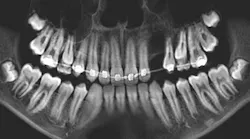

A healthy 6-year-old male presented for a routine dental visit. The patient was taking no medications and had no known medical allergies.

Dental history included a small amount of caries with an anterior crossbite (end to end), as well as a habit of biting his lower lip with his teeth. The patient had been seen three times in the last three years; the parents did not bring the child to the dental office for regular checkups. At a visit six to seven months ago, the patient had a sore lower lip from biting it all day. There were no soft-tissue findings at the time.

The likely diagnosis in this case is oral mucocele, aka mucous retention cyst, from a blocked duct, secondary to chronic lip biting. It is hoped that the patient will eventually have a biopsy so a definitive diagnosis can be rendered. The patient's mom has been advised to be diligent in reminding her son to cease biting his lip.